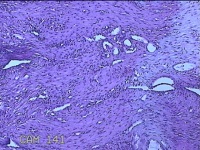

宫腔粘连带

性别

女

年龄

44岁

临床诊断

稽留流产 宫颈炎 宫腔粘连? 宫颈息肉

一般病史

停经1月,发现胚胎停育半天。

标本名称

大体所见

灰白暗红色不规则碎组织1.3x1.2x0.3cm一堆。